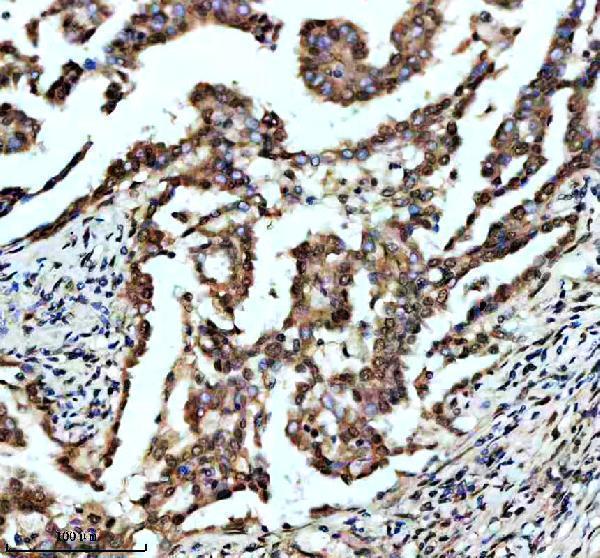

Expressed in lung and placenta.